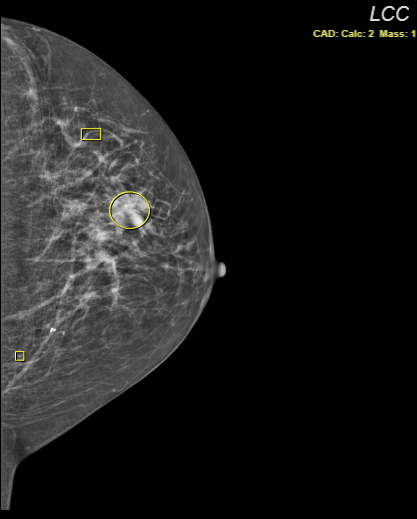

Mammography CAD objects

SUITESTENSA supports the display of Mammographic Computer-Aided Detection objects.

CAD markers are displayed on the image. See the Mammo CAD markers and outlines table below for information on what each marker means.

Mammo CAD markers and outlines

Note that CAD outlines can be enabled or disabled by administrators. Certain vendors may not display markers or outlines for CAD objects. See Vendor-specific display below for more information.

Figure 1 : CAD marker (left) and CAD outline (right)

Calcification cluster |

Individual calcification |

Mass (density) |

Mass with calcifications |

Vendor-specific display

iCAD2

Only outlines are displayed for mass and calcification clusters (that is, markers are not shown).

Mammo CAD indicators

| CAD: Calc: 2 Mass: 1 |

CAD markers displayed Shown in the viewport to indicate that CAD markers are displayed. The numbers represent the count for every type of displayed marker. |